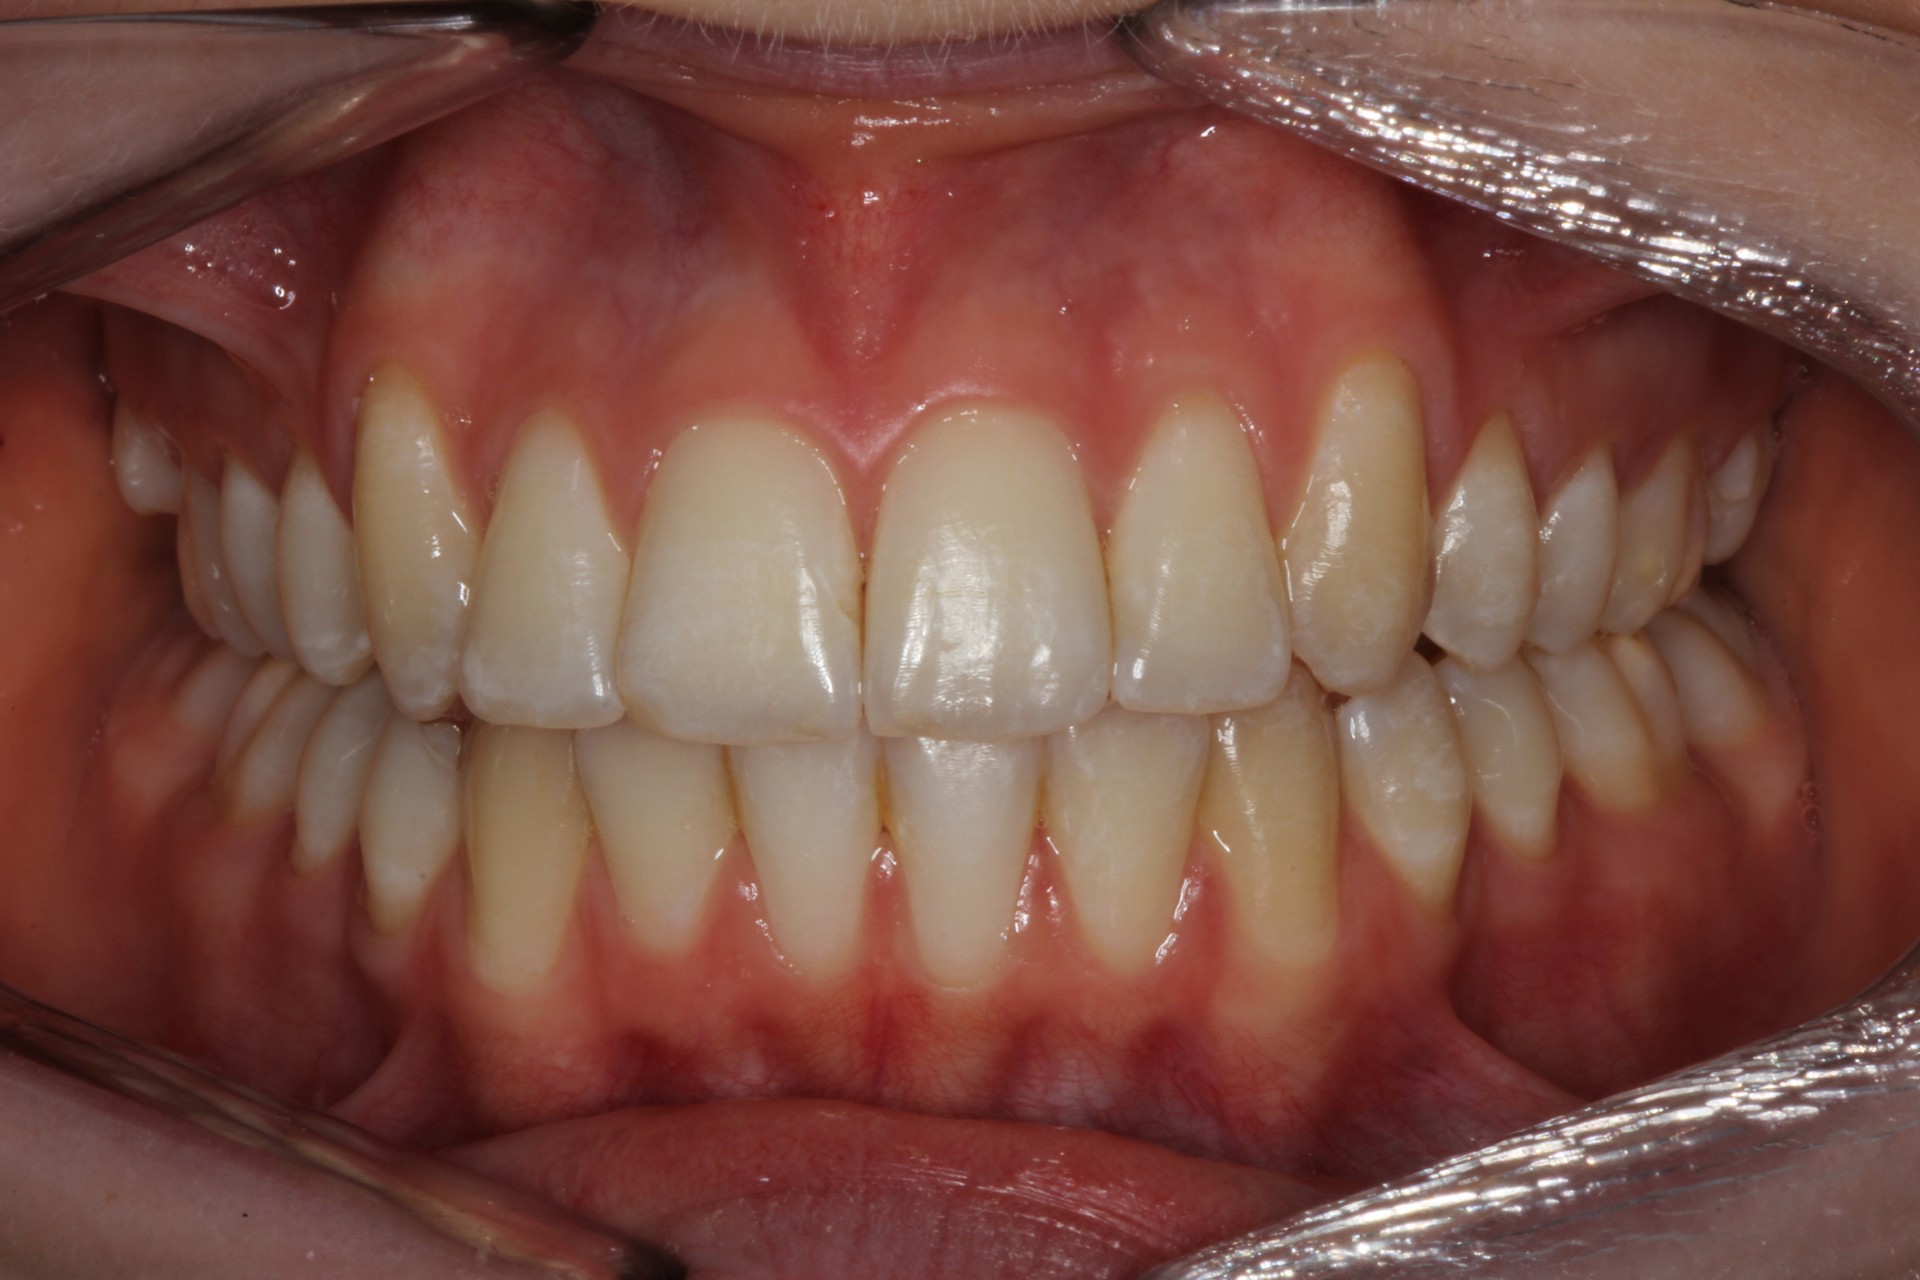

Protruding front teeth with midline diastema – Child case